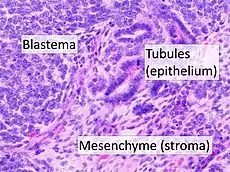

| High magnification micrograph showing the three elements of Wilms' tumor. H&E stain. | |

Pathologically, a triphasic nephroblastoma comprises three elements:[11]

- blastema

- mesenchyme (stroma)

- epithelium

Wilms' tumor is a malignant tumor containing metanephric blastema, stromal and epithelial derivatives. Characteristic is the presence of abortive tubules and glomeruli surrounded by a spindled cell stroma. The stroma may include striated muscle, cartilage, bone, fat tissue, and fibrous tissue. Dysfunction is caused when the tumor compresses the normal kidney parenchyma.

The mesenchymal component may include cells showing rhabdomyoid differentiation or malignancy (rhabdomyosarcomatous Wilms).